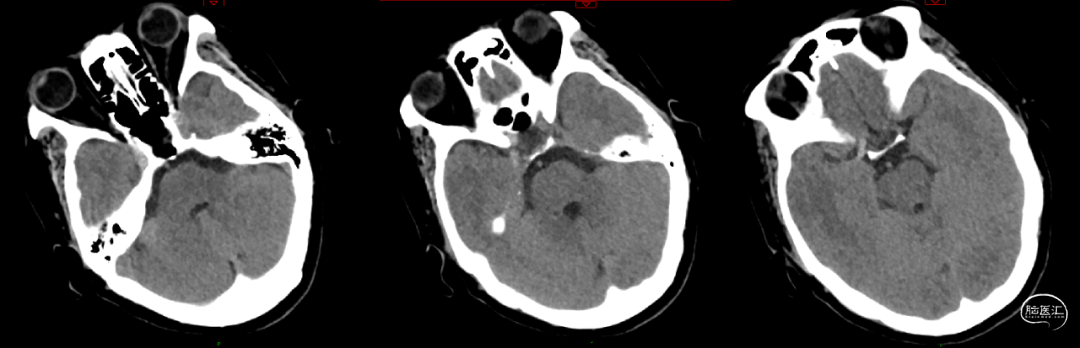

术前影像学

术前颅脑CT:R-ICA、M1高密度影